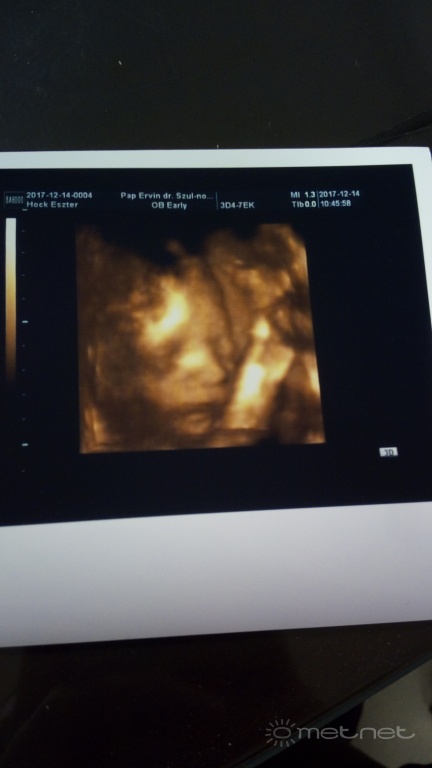

Feltöltő: StormCaster Feltöltötte: 2018-01-25 11:45:51 Exif adatok: Fényképező: thor Dátum: 2017:12:14 09:57:26 Záridő: 0.060002 s Rekesz: 2 Érzékenység: 111 Felhasználó további képei |